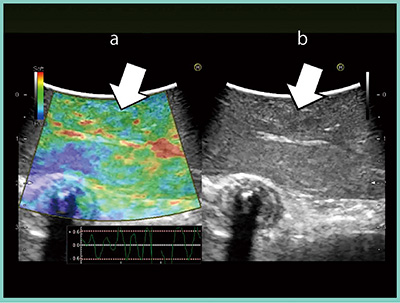

症例3は,大腸がん肝転移術後経過観察のCTとMRIで,S7とS3に新規病変が見つかった。小結節ではあるがサイズが増大していたため,大腸がん肝転移を疑い切除した。術中造影超音波では,境界明瞭な腫瘍として描出されたが,造影超音波前に行ったRTEでは,腫瘍は青く描出されていなかった(図4a)。最終的に,肉眼的また病理学的にも血管腫と診断されたことから,RTEでの診断が正しい症例であった。

図4 症例3:RTEによる肝転移/血管腫の鑑別